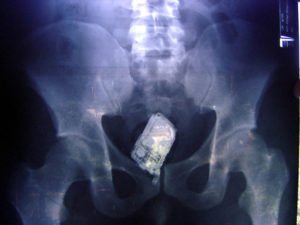

Врач может отыскать инородное тело в заднем проходе во время пальцевого исследования прямой кишки. Также инородные тела определяются путем рентгенологического исследования.

Для того, чтобы выяснить, повреждена или нет стенка толстой кишки, проводится инструментальное обследование — ректороманоскопия и рентгенография (ирригоскопия).

Если пациент указывает на наличие инородного предмета в прямой кишке, при помощи пальцевого обследования возможно определить его местонахождение, форму, размеры и подвижность.

В некоторых случаях посредством пальцевого исследования удается извлечь инородный предмет, так как чаще всего инородное тело располагается в среднем сегменте прямой кишки.

Для выявления постороннего предмета в прямой кишке может потребоваться использование ректальных зеркал или аноскопии.

Затем может потребоваться обследование с помощью ректоскопа, а также рентген брюшной полости для определения точного расположения инородного предмета.